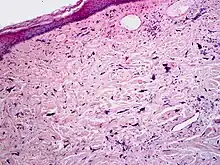

Micrograph of pleomorphic fibroma. Cell-depleted, fibrous connective tissue with atypical fibroblasts